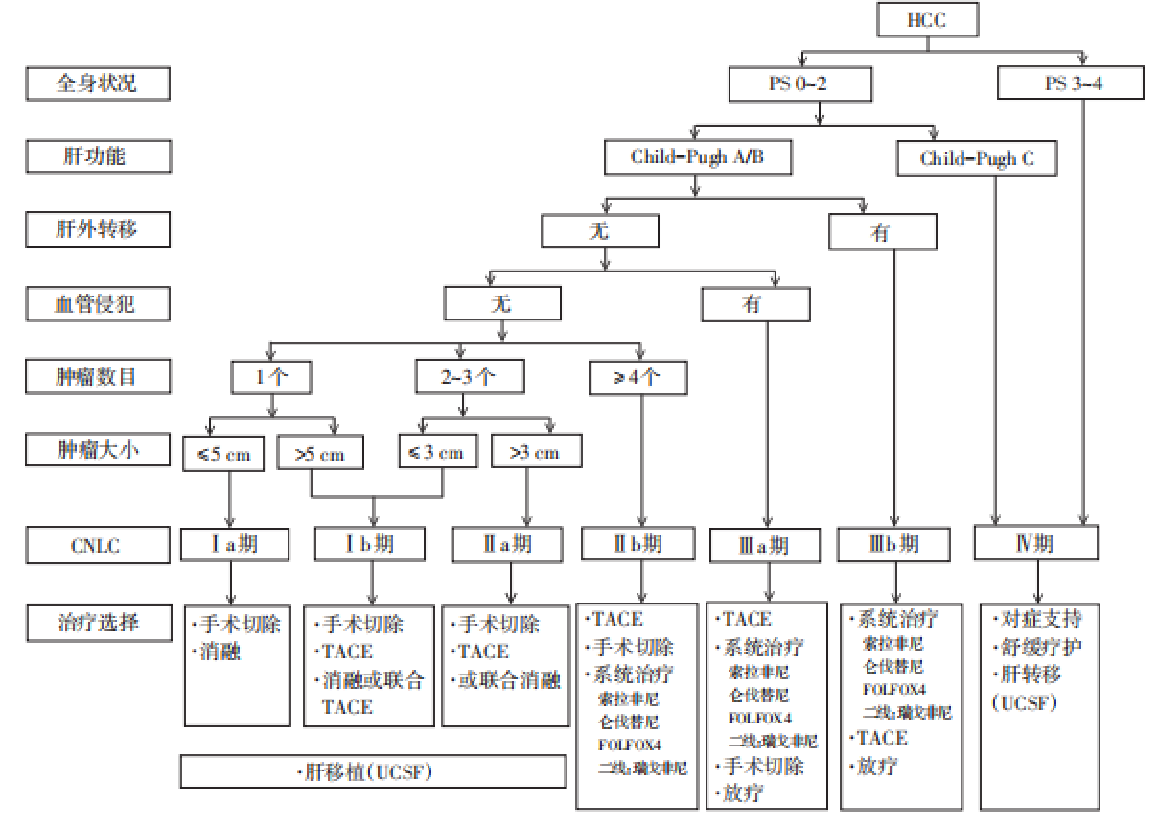

我国原发性肝癌诊疗规范(2019)的治疗方案: